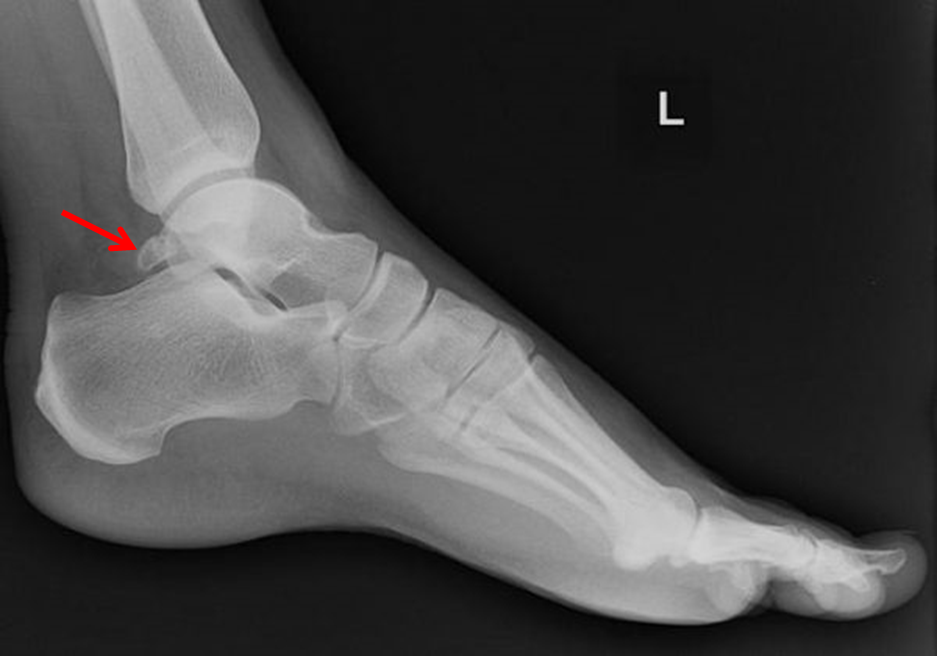

Hình ảnh gai sau xương sên trên X Quang

Hình 1: Bệnh nhân Nam 28 tuổi

A & B: Khối gai xương sau xương sên trên X quang trước mổ và hình ảnh nội soi trong mổ (mũi tên đỏ)

C: Hình ảnh tổn thương viêm gân gấp ngón cái dài trong mổ

Hình ảnh sau mổ trên X quang và vết mổ

Hình 2: Bệnh nhân Nam 45 tuổi

A: Hình ảnh khối gai xương trên X quang trước mổ (mũi tên đỏ)

B: Hình ảnh khối gai xương trong nội soi (mũi tên đỏ) và hình ảnh viêm gân gấp dài ngón cái và bao khớp sau

C: Hình ảnh X quang sau mổ